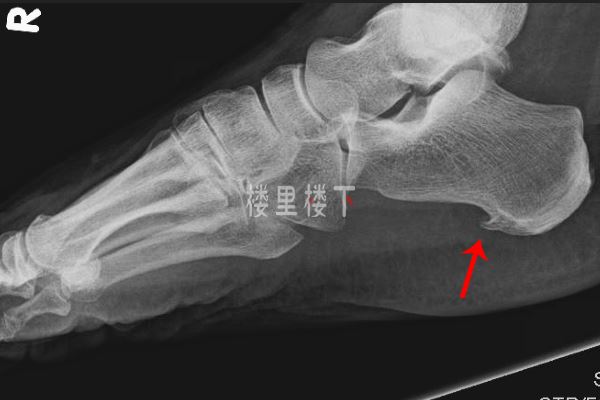

我們知道骨刺是骨質(zhì)增生的俗稱,通常出現(xiàn)在骨頭關(guān)節(jié)的地方,比如膝蓋,比如腳后跟,特別是對(duì)于常年肥胖的人群,腳跟受力比較大,所以六十歲后長骨刺的幾率比較大,長了骨刺會(huì)對(duì)局部血液循環(huán)有影響,骨刺凸起的部分可能會(huì)壓到神經(jīng),然后就產(chǎn)生嚴(yán)重的疼痛。